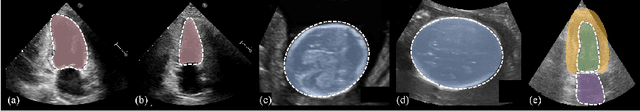

Abstract:Ultrasound (US) image segmentation is an active research area that requires real-time and highly accurate analysis in many scenarios. The detect-to-segment (DTS) frameworks have been recently proposed to balance accuracy and efficiency. However, existing approaches may suffer from inadequate contour encoding or fail to effectively leverage the encoded results. In this paper, we introduce a novel Fourier-anchor-based DTS framework called Fourier Feature Pyramid Network (FFPN) to address the aforementioned issues. The contributions of this paper are two fold. First, the FFPN utilizes Fourier Descriptors to adequately encode contours. Specifically, it maps Fourier series with similar amplitudes and frequencies into the same layer of the feature map, thereby effectively utilizing the encoded Fourier information. Second, we propose a Contour Sampling Refinement (CSR) module based on the contour proposals and refined features produced by the FFPN. This module extracts rich features around the predicted contours to further capture detailed information and refine the contours. Extensive experimental results on three large and challenging datasets demonstrate that our method outperforms other DTS methods in terms of accuracy and efficiency. Furthermore, our framework can generalize well to other detection or segmentation tasks.

Abstract:The Segment Anything Model (SAM) is the first foundation model for general image segmentation. It designed a novel promotable segmentation task, ensuring zero-shot image segmentation using the pre-trained model via two main modes including automatic everything and manual prompt. SAM has achieved impressive results on various natural image segmentation tasks. However, medical image segmentation (MIS) is more challenging due to the complex modalities, fine anatomical structures, uncertain and complex object boundaries, and wide-range object scales. Meanwhile, zero-shot and efficient MIS can well reduce the annotation time and boost the development of medical image analysis. Hence, SAM seems to be a potential tool and its performance on large medical datasets should be further validated. We collected and sorted 52 open-source datasets, and built a large medical segmentation dataset with 16 modalities, 68 objects, and 553K slices. We conducted a comprehensive analysis of different SAM testing strategies on the so-called COSMOS 553K dataset. Extensive experiments validate that SAM performs better with manual hints like points and boxes for object perception in medical images, leading to better performance in prompt mode compared to everything mode. Additionally, SAM shows remarkable performance in some specific objects and modalities, but is imperfect or even totally fails in other situations. Finally, we analyze the influence of different factors (e.g., the Fourier-based boundary complexity and size of the segmented objects) on SAM's segmentation performance. Extensive experiments validate that SAM's zero-shot segmentation capability is not sufficient to ensure its direct application to the MIS.